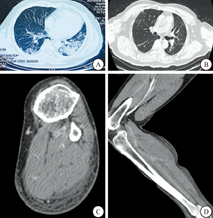

1#患者是一位81岁的男性,患者因疲劳、肌肉酸痛和厌食症状2周入院。他有20多年糖尿病和高血压的既往病史。患者与感染COVID-19的家庭成员有接触史,1周后CT提示病毒性肺炎。SARS-CoV-2的核酸检测阳性证实诊断。他接受了口服抗病毒治疗并在家中隔离。然而他的病情恶化,在另一家医院住院了1周后转入武汉大学中南医院的重症监护室。他接受综合治疗包括静脉注射抗生素、输氧和口服药物以控制高血压和血糖,皮质类固醇用于控制细胞因子风暴和稳定体内平衡。他的体温波动在正常至37.4 ℃之间。但是他的状况没有任何改善。他于2月20日死于多器官衰竭,临床病程为24 d(图1)。2#患者因乏力、纳差、肌肉酸痛1月余及左下肢肿胀半月余入院(图2)。1月11日无明显诱因出现全身肌肉酸痛、纳差、不明原因乏力,否认发热,恶心呕吐等不适。1月21日外院CT提示双肺见斑片及磨玻璃密度影,胸膜下病灶较密集,密度不均且边缘不清。1月25日重复CT提示两肺见斑片状磨玻璃密度影,与前次相比双肺病灶稍增厚。1月28日两肺见斑片状磨玻璃密度影,部分病灶有吸收。1月28日新型冠状病毒RNA检测阴性。已给予抗病毒治疗(具体不详)。在外院治疗过程中出现左下肢肿胀,外院B超提示左侧下肢动脉血栓合并静脉血栓,给予口服抗凝(利伐沙班+氯吡格雷)治疗。2月13日因症状加重,患者再次被送往该医院接受口服药物治疗。患者主诉咳嗽,左下肢色素沉着和水肿,但没有呼吸困难和呼吸急促,于2月18日转入武汉大学中南医院,胸部CT检查显示有磨玻璃影,左、右下肺叶的胸膜下区域仍可见实变。2月20日下肢血管CT增强显示左下肢有腘动脉血栓形成(图3)。2月22号胸部复查CT示左肺下叶及右肺下叶胸膜下区可见磨玻璃影及实变影,左肺下叶病变内可见含气支气管影。2月24日行大腿中下段截肢手术,术后恢复良好,于3月10号出院。

回顾患者1#的腓肠肌穿刺组织检查显示出轻微的慢性变化(图4)。在低倍镜下,不规则和萎缩的肌纤维与正常形状的肌纤维交织在一起,酷似镶嵌排列的大理石地面(图3A,图3B,图3C)。LCA和CD68阳性染色证实极轻微的炎性细胞浸润,可见局灶性纤维化和血管充血。ACE2突出显示不规则和萎缩的肌纤维,而在正常的对照肌纤维中显示胞膜和胞质的混合表达模式(图4D)。从患者2#的左下肢截除标本获得多块组织,包括动脉、静脉、神经、皮肤、滑膜组织、肌肉和软骨。病理结果显示动脉血栓形成和血管内皮细胞脱失,还观察到残留表皮过度角化、棘层松解以及表皮中水泡的形成。在真皮浅表小血管中可见微血栓。在皮下脂肪组织中发现坏死性血管炎和血栓形成,局部基质的黏液样改变。在送检的神经、滑膜组织和软骨标本中未见炎性细胞浸润和结构变化。至于骨骼肌的变化轻微(图5),可见核链和散在的中央核肌纤维(图5A,图5B)及肌纤维坏死和轻微炎症(图5C,图5D)。浸润的炎细胞主要是组织细胞和淋巴细胞,分别通过CD68和LCA染色证实。此外,两名患者的肌肉组织中SARS-CoV-2的RT-PCR检测均为阴性。